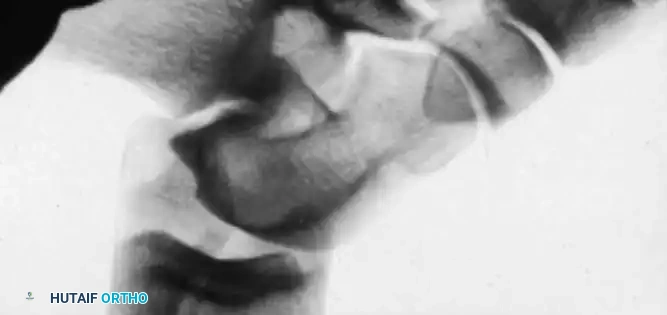

Anteroposterior Stress Test (Anterior Drawer Sign)

Broström, Castaing, and Delplace heavily emphasized the anterior drawer sign as the primary indicator of an ATFL tear.

Clinically, the maneuver is performed by placing the tip of the thumb on the anterior aspect of the lateral malleolus while palpating the lateral talar process with the base of the thumb. With gentle anterior stress applied to the heel while stabilizing the tibia, the surgeon assesses the degree of anterior translation of the talus relative to the tibial plafond.

Tohyama et al., in a rigorous cadaveric study, demonstrated that applying 30 N of force during the anteroposterior stress test produced a more reliable injured-to-normal displacement ratio than applying 60 N of force. They recommended utilizing a relatively low-magnitude load when evaluating ATFL integrity to prevent secondary restraints from masking the laxity.

Anderson and LeCocq stated that 3 mm of forward talar displacement on stress radiographs is pathological and indicates lateral ligamentous rupture. However, the clinical sensation of the talus subluxating out of the mortise (the "suction sign") is often more diagnostically valuable than absolute millimeter measurements.